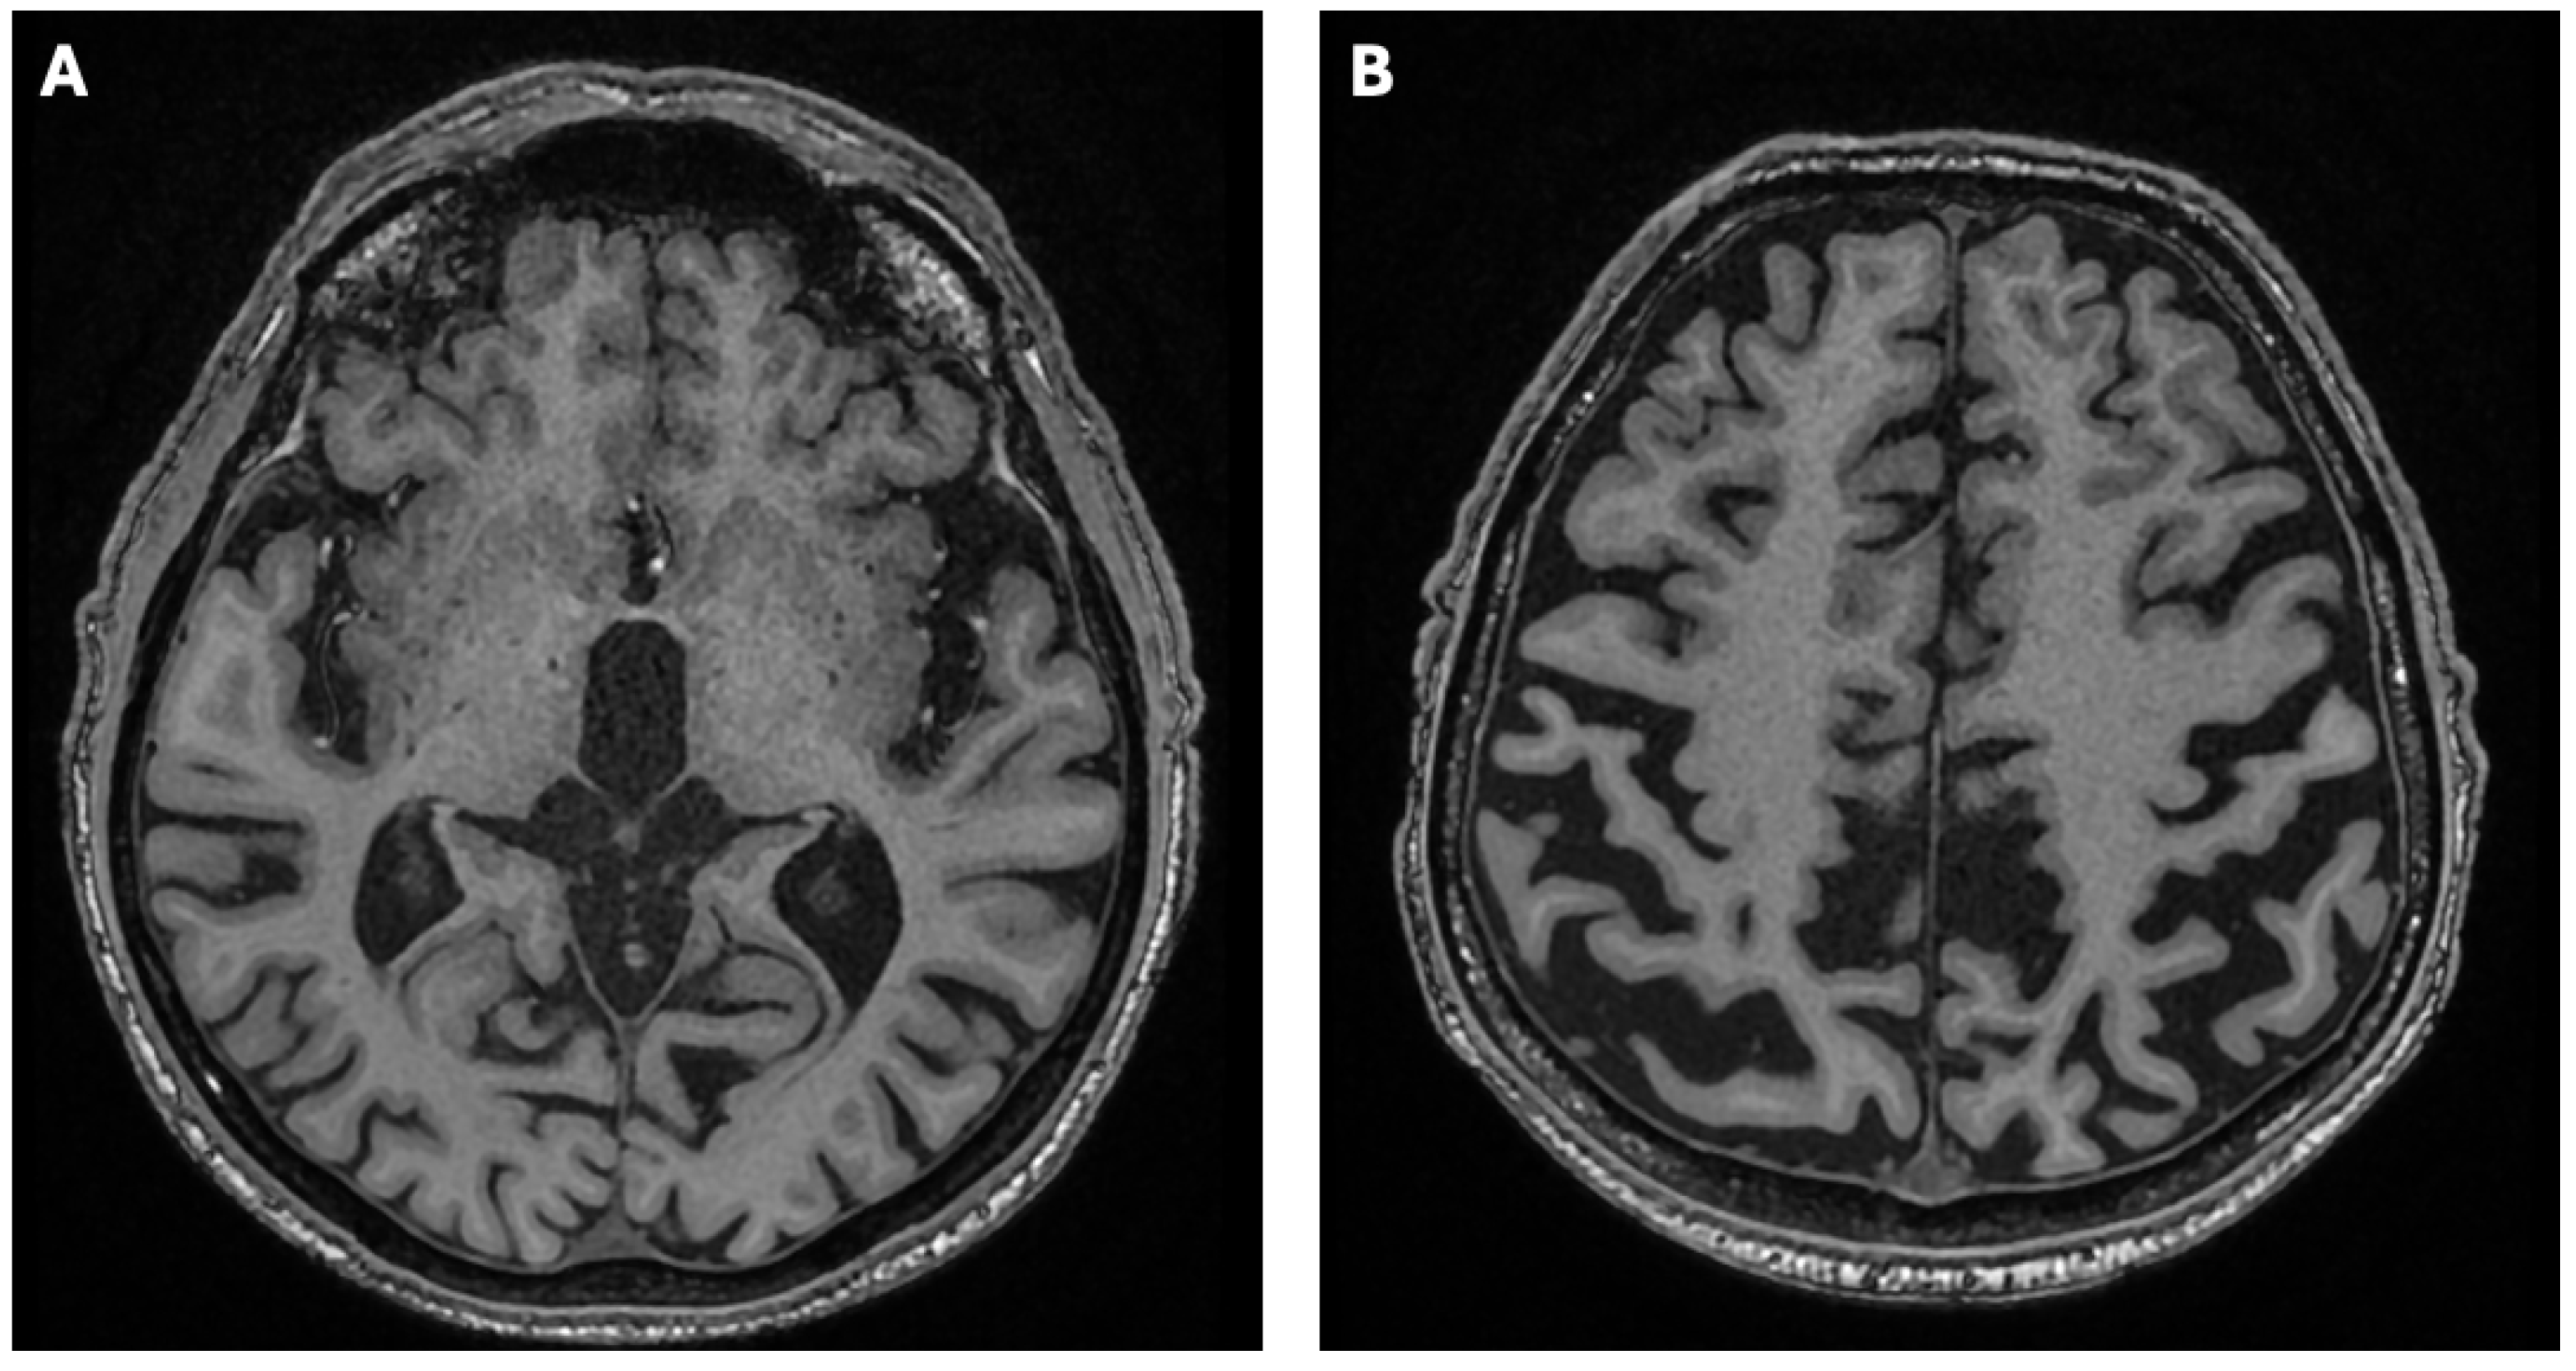

2. Case Report